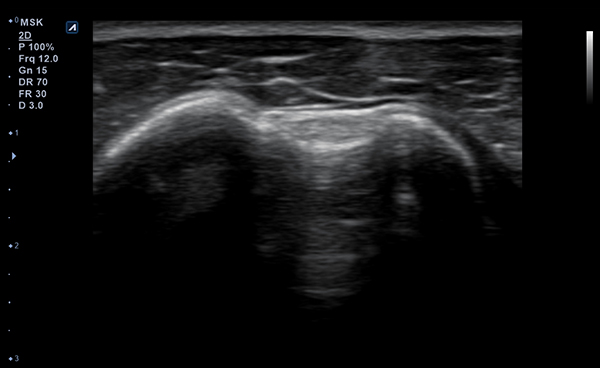

Con Convex y Linear, dos tipos de transductores, puede escanear tanto las

partes más superficiales como las más profundas del cuerpo humano.

Los transductores tienen un amplio rango de aplicaciones y pueden ser utilizados en

una gran variedad de situaciones clínicas.

- Frequency3-12 MHz

- Dimension (height/width/depth)25.2 / 62.5/ 150mm

- Weight 175g

- Field of view 38.4mm

- Max depth10 cm

- Imaging modesB-mode, CF, M, PW, PD

- DisplayMicrosoft Surface

- Battery300 min